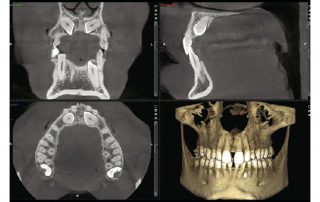

Premium image quality

Packed with intelligent high-tech solutions and algorithms, all Planmeca CBCT units offer an effortless imaging process and crystal-clear images — and at a low dose. These units have been designed to prevent human error with options for correcting movement as well as noise and artefact reduction.

Comprehensive imaging software

Planmeca Romexis® is the leading software platform for dentistry. It provides a rich set of tools to meet the imaging requirements set by any dental facility – from a small clinic to a large hospital. The software supports all 2D and 3D dental imaging as well as CAD/CAM workflows with its extensive range of tools.